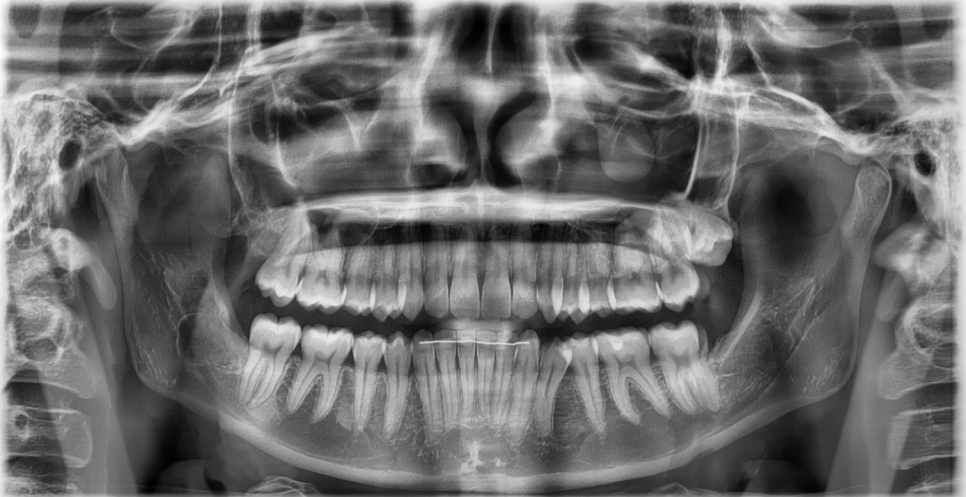

In your 20s, the bone is relatively soft,

and the tooth is not strongly fused to the bone,

so extraction is generally less difficult.

On the other hand, as you get into your 30s and beyond,

the bond between the bone and the tooth becomes stronger,

and even with the same wisdom tooth,

the extraction time, incision range, and recovery period often become longer.

The actual condition of the tooth,

its position inside the gum,

the distance from the nerve,

and even the range used when smiling or chewing

all need to be checked directly for an accurate judgment.